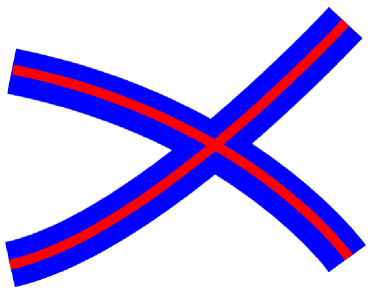

Following Cetingul et al. (2014), we consider here the problem of segmenting or clustering two 2D synthetic fiber tracts in the domain. To generate the fibers, six points are randomly chosen in the colored region of Figure 8a. Two cubic splines passing through and , respectively, are set to be the center of the fibers (cf., red curves in Figure 8b). Fibers are defined as the curved bands around the splines with bandwidth (cf., blue region in Figure 8b).

Given a pair of such fibers, the next step is to map each pixel (e.g., both red and blue ones in Figure 8b) to a point (SRdODF) in . To this end, the software code provided by Canales-Rodriguez et al. (2013) is used to generate SRdODFs on , where diffusion images at gradient directions, with baseline image and , are considered. The dimensionality of the generated SRdODFs corresponds to directions. Moreover, Gaussian noise was added in the ODF-generation mechanism, resulting in a signal-to-noise ratio (more details on the construction can be found in Cetingul et al. (2014)). Typical noise levels for real-data brain images are considered: , and (i.e., ).